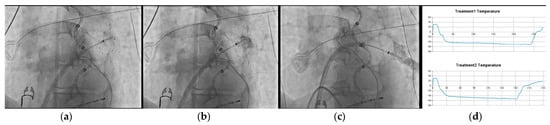

- In several clinical scenarios, the use of this new CB feature has helped the operator to reach an easier PVI, such as in cases with common PV trunks, accessory PVs, and funnel-shaped PV ostia.

4.2. Case-Based Approach